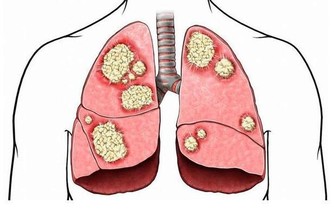

7、濫用抗生素

濫用抗生素有可能破壞腸道先天免疫力,這也是引起耐抗生素細菌感染的原因。埃里克·帕爾默領導的紐約“斯隆·凱特林癌症研究所”的研究人員試驗後發現,這是一種廣泛使用抗生素導致的並發症,將使患者的身體健康受到更大傷害。